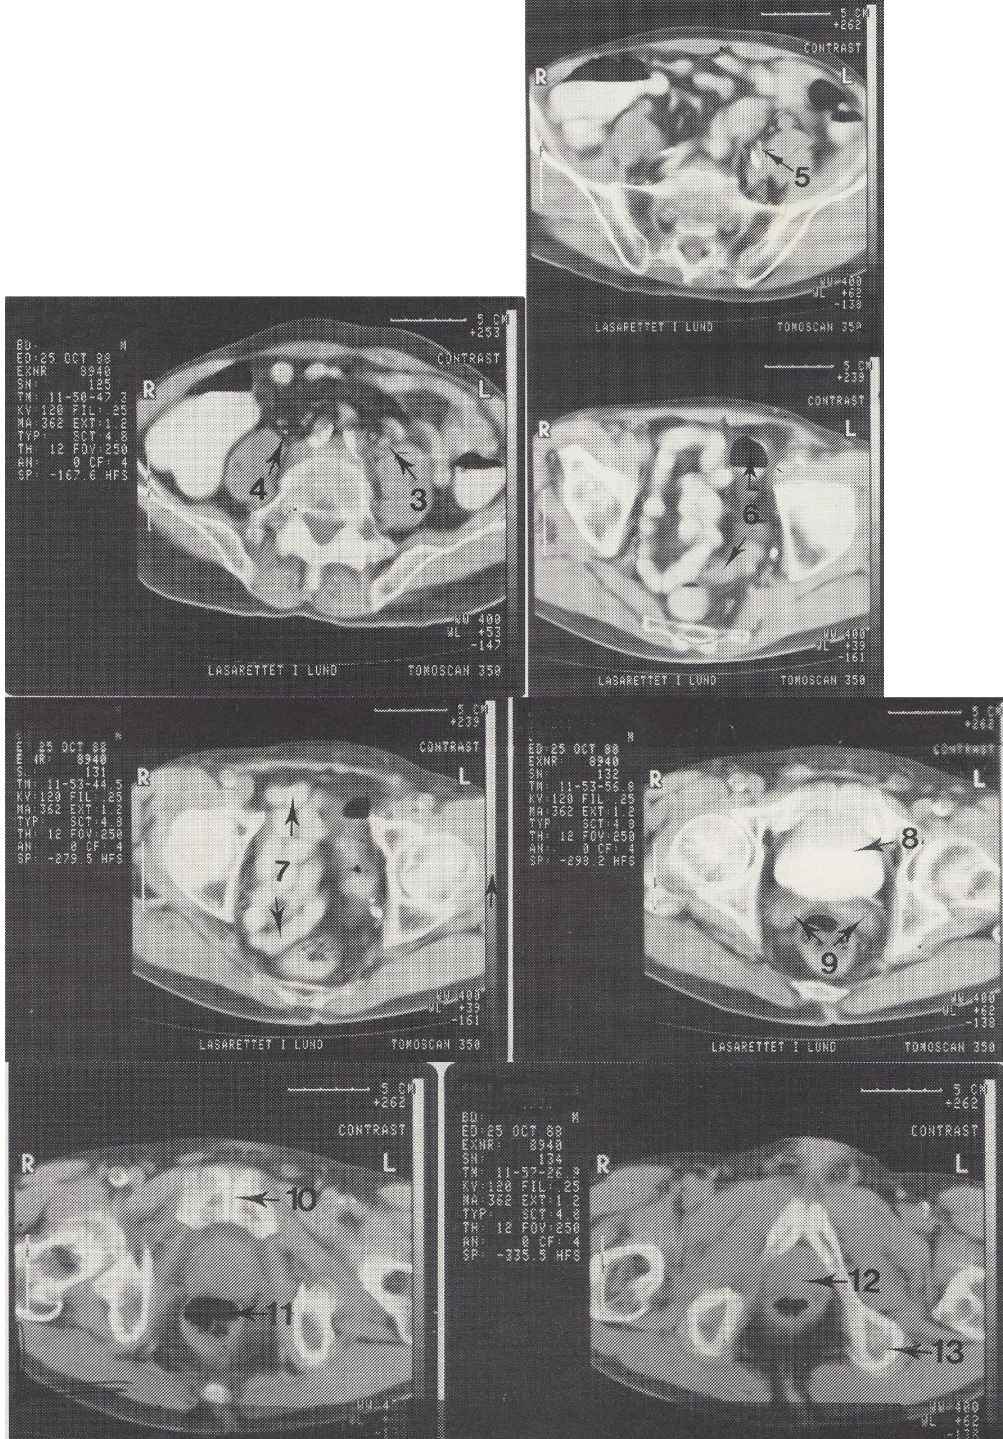

1

Aorta abdominalis (kalcifikuota pilvinė aorta)

2

M. psoas major (didysis juosmens raumuo)

3

Ureter sinister (kairysis šlapimtakis, šiek tiek praplėstas)

4

Ureter dexter (dešinysis šlapimtakis)

5

A. iliaca interna sin. (kairioji vidinė klubo arterija)

6

Colon sigmoideum (riestinė žarna)

7

Ileum kilpos dubenyje (tuščiosios žarnos kilpos)

Metodika

KT pjūviai nuo juosmens slankstelių iki gaktinės sąvaržos apačios. Suleistas intraveninis kontrastas (išryškina šlapimo takus) ir išgertas kontrastas (išryškina žarnyną).

Radiniai

Gausūs apkalkėjimai (kalcifikatai) aplink pilvinę aortą ir vidines klubo arterijas. Kairysis šlapimtakis matomas priešais m. psoas major, jis šiek tiek išsiplėtęs.